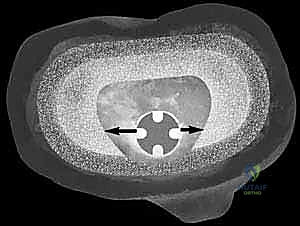

يعتمد الدكتور هطيف على أحدث تقنيات التصوير الطبي، بما في ذلك الأشعة السينية الرقمية (Digital X-rays) في وضعيات الوقوف، والتصوير المقطعي المحوسب (CT Scan) ثلاثي الأبعاد لتقييم حجم العظم المتبقي بدقة متناهية. كما يتم إجراء فحوصات دم شاملة وسحب سائل من الركبة (Aspiration) لاستبعاد وجود أي عدوى بكتيرية خفية.

3. تنظيف العظم وتقييم العيب (Debridement and Assessment)

بعد إزالة المفصل، يتم تنظيف العظم بالكامل من أي أنسجة ملتهبة أو أسمنت متبقي. هنا، تتجلى الرؤية الحقيقية لحجم العيب العظمي (AORI Type II أو III). يتم قياس الفجوات العظمية بدقة باستخدام قوالب تجريبية.

4. تحضير الساق وتركيب الدعامات المعدنية (Tibial Preparation and Augmentation)

لتعويض العظم المفقود وإعادة مستوى المفصل (Joint Line) إلى ارتفاعه التشريحي الطبيعي، يقرر الدكتور هطيف نوع الدعامة المعدنية المناسبة:

* إذا كان العيب سطحياً وفي جهة واحدة، تُستخدم الكتل أو الأوتاد المعدنية (Wedges/Blocks) التي تُثبت بأسفل الغرسة الجديدة.

* إذا كان العيب كبيراً وعميقاً في المركز، تُستخدم المخاريط أو الأكمام المسامية (Cones/Sleeves). يتم حفر العظم التالف بشكل هندسي دقيق ليحتضن هذا المخروط المعدني الذي يوفر أساساً صخرياً متيناً.